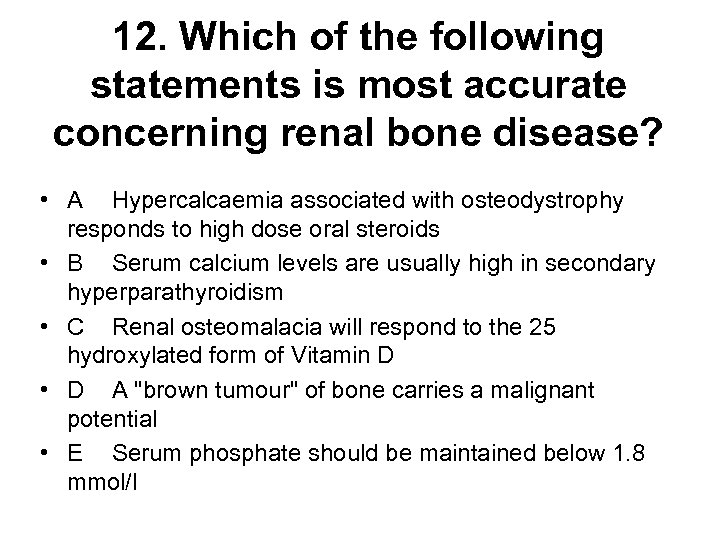

12. Which of the following statements is most accurate concerning renal bone disease? • A Hypercalcaemia associated with osteodystrophy responds to high dose oral steroids • B Serum calcium levels are usually high in secondary hyperparathyroidism • C Renal osteomalacia will respond to the 25 hydroxylated form of Vitamin D • D A "brown tumour" of bone carries a malignant potential • E Serum phosphate should be maintained below 1. 8 mmol/l

12. Which of the following statements is most accurate concerning renal bone disease? • A Hypercalcaemia associated with osteodystrophy responds to high dose oral steroids • B Serum calcium levels are usually high in secondary hyperparathyroidism • C Renal osteomalacia will respond to the 25 hydroxylated form of Vitamin D • D A "brown tumour" of bone carries a malignant potential • E Serum phosphate should be maintained below 1. 8 mmol/l

12. Which of the following statements is most accurate concerning renal bone disease? • A Hypercalcaemia associated with osteodystrophy responds to high dose oral steroids • B Serum calcium levels are usually high in secondary hyperparathyroidism • C Renal osteomalacia will respond to the 25 hydroxylated form of Vitamin D • D A "brown tumour" of bone carries a malignant potential • E Serum phosphate should be maintained below 1. 8 mmol/l

12. Which of the following statements is most accurate concerning renal bone disease? • A Hypercalcaemia associated with osteodystrophy responds to high dose oral steroids • B Serum calcium levels are usually high in secondary hyperparathyroidism • C Renal osteomalacia will respond to the 25 hydroxylated form of Vitamin D • D A "brown tumour" of bone carries a malignant potential • E Serum phosphate should be maintained below 1. 8 mmol/l

Clinical features • May be none • Soft tissue calcification - itch, red eye, calciphylaxis and (probably) increased risk CHD due to coronary calcification • 2 y hyperpara - high PO 4 with low Calcium, may cause bone pain, fractures • Osteomalacia - bone pain, rickets in childhood, proximal myopathy, fractures NB Osteitis fibrosa cystica is the term used to describe the appearance of bone in 2 y hyperpara. In severe cases, proliferation of osteoclasts results in cyst formation in bone called a “brown tumour” which is not premalignant

Clinical features • May be none • Soft tissue calcification - itch, red eye, calciphylaxis and (probably) increased risk CHD due to coronary calcification • 2 y hyperpara - high PO 4 with low Calcium, may cause bone pain, fractures • Osteomalacia - bone pain, rickets in childhood, proximal myopathy, fractures NB Osteitis fibrosa cystica is the term used to describe the appearance of bone in 2 y hyperpara. In severe cases, proliferation of osteoclasts results in cyst formation in bone called a “brown tumour” which is not premalignant

Treatment of renal bone disease • Alfacalcidol or calcitriol (1: 25 DHCC) to keep calcium normal and PTH 2 -4 times ULN after controlling PO 4 • Cinacalcet (Mimpara) for severe 2 y HPT • Parathyroidectomy for 3 y HPT, uncontrollable itch with high Ca-PO 4 product and calciphylaxis (skin necrosis) NB Hypercalcaemia assoc with renal bone disease does not respond to oral steroids and renal osteomalacia does not respond to 25 OHD

Treatment of renal bone disease • Alfacalcidol or calcitriol (1: 25 DHCC) to keep calcium normal and PTH 2 -4 times ULN after controlling PO 4 • Cinacalcet (Mimpara) for severe 2 y HPT • Parathyroidectomy for 3 y HPT, uncontrollable itch with high Ca-PO 4 product and calciphylaxis (skin necrosis) NB Hypercalcaemia assoc with renal bone disease does not respond to oral steroids and renal osteomalacia does not respond to 25 OHD